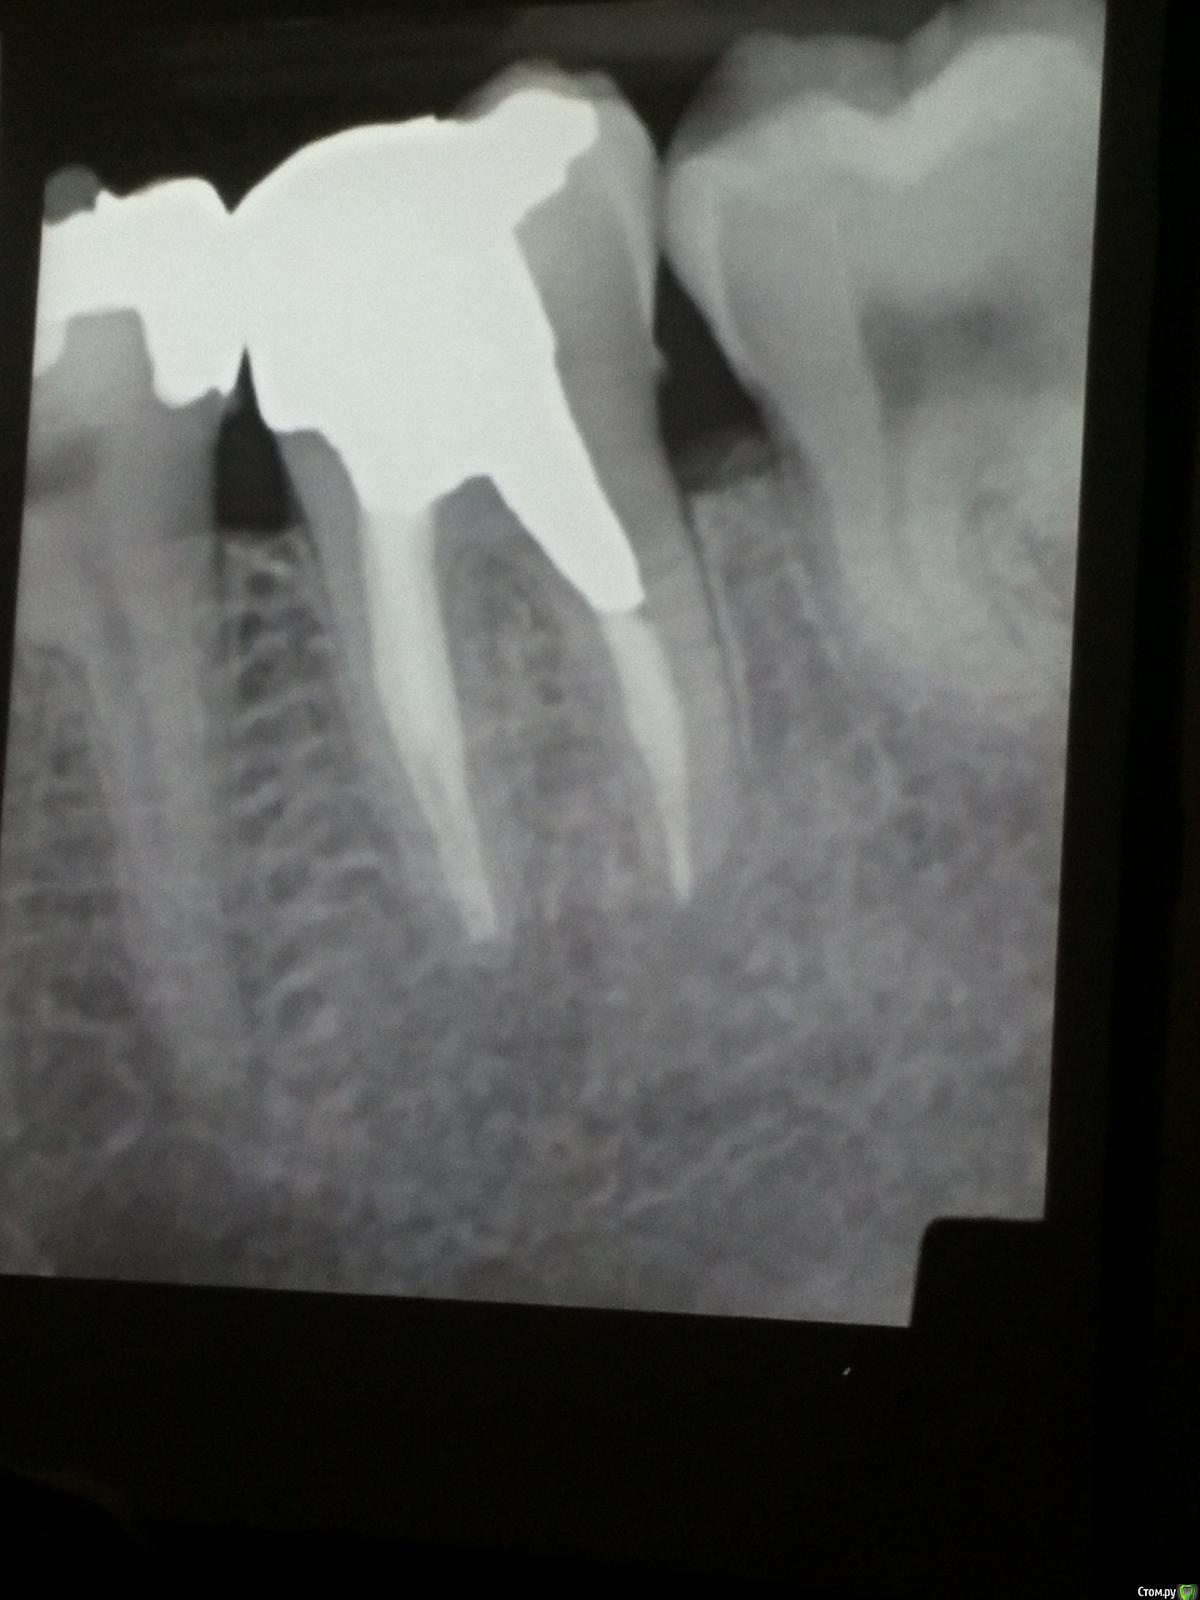

Популярный пост Kolchanov Опубликовано 11 марта, 2017 Популярный пост Поделиться Опубликовано 11 марта, 2017 (изменено) Товарищи, скажу я вам...........Вкратце. Может я где-то что-то и приврал, надеюсь, кто еще был, поправят. Честно говоря немного прибалдел от уровня Доктора. Очень, очень высоко! Приедет еще раз, пойду еще. 1) Фиссуры зондирует острым зондом и выпиливает все дотла. По факту у него уже пломбы, а не герметизация.2) Bite-wing у первичных пациентов всегда.3) Если кариес диагносцирован, то лечить его, пофиг какой он там. Эмали, дентина…4) Препарирует до твердого (или до вскрытия J ). CAD, СID… в топку. Кариес маркером не пользуется, проверяет острым зондом/экскаватором. Вычищает все дотла. Считает, что даже небольшое количество бактерий в дентине под пломбой вызывают хроническое воспаление в пульпе. С его слов у него на контроле где-то 500 вскрытий, не удивительно при таком подходе к очистке.5) Тщательная изоляция. Коффер порвался – меняет. Большое значение герметичности реставрации. под замену6) Критерии обратимости и необратимости.Гистологически, обратимый тот, что без абсцессов в пульпе, но клинически это понять нельзя, только предположить.Здесь был бы обратимый, если бы не удалил. Нет микробов в пульпе. Линия - граница обработки.Покрытие 27 лет назад. Dycal, СИЦ, композит. От дайкала одно воспоминание.7) Вскрылись. Размер перфорации, возраст и прочее не играют роли, важно только состояние пульпы, т.е. диагноз.Примеры перфораций.8) Кровотечение останавливает стерильным ватным шариком. Если останавливается, то покрытие, если нет, то пульпотомия или пульпэктомия.9) Использует гидроокись кальция (порошок), перекрывает Dycal или СИЦ. Потом восстановление Нередко под IRM, потом все убирает (через пару-тройку месяцев) и смотрит, что получилось. Порой приходится повторять! Использует и МТА, его тоже убирает.10) Наблюдение 6мес, 1 год, 2…. Все может провалиться и через месяц и через 24 года.Примеры проваловНиже - 24 года спустя появилась дуля. 11) Неравномерная облитерация полости зуба на RG (после покрытия) – признак текущего хронического воспаления, где-то остались микробы. Рекомендует эндо.12) Мостик который образуется – это не дентин! И одонтобласты не регенерируют и новые не образуются. Что это такое он и сам не знает, но раз это твердые ткани, то и наплевать.Вот фиолетовое это дентинные опилки вмурованные в розовую ткань бог знает кем сформированную.13) Пульпотомия в зубах с несформированной верхушкой и в сформированных, при подозрении на частичное поражение коронковой пульпы. Иссекается стерильным алмазным бором часть пульпы, гидроокись, временная пломба на 90 дней, после повторное раскрытие, оценка результата, восстановление в случае формирования твердых тканей. Гипохлоритом можно мыть, можно не мыть, если мыть, то 0,5-1%.14) В апикальной части пульпа чаще витальна, чем нет.15) Периапикальные поражения возникают по причине поступления токсинов микробов с током крови, а не самих бактерий.16) За апикальные расширения в полностью некротических случаях. Надо механически отодрать биопленку и срезать инфицированный дентин. На ирриганты надежды мало.17) Биопленка на поверхности в 6% случаев.Синенькие пид@расы18) Обработку проводить нежно, краун-даун. Чередовать с H-файлом, чтобы посмотреть докуда распространяется некроз.19) Патенси в витальных кейсах не колоть, сохранять витальную пульпу в констрикции!Формирование еще большего сужения в констрикции за счет сохранения витальной пульпы. Изменено 11 марта, 2017 пользователем Kolchanov 31 Ссылка на комментарий

Популярный пост Kolchanov Опубликовано 12 марта, 2017 Автор Популярный пост Поделиться Опубликовано 12 марта, 2017 Второй день.1) Дезинфекция зуба и раббер дама перед работой. Вначале установка системы, потом протирка тампоном 30% перекиси, потом протирка всего йодинолом. Потом преп, потом повторение и только потом доступ к к/к. Все старые реставрации надо убрать, кариес убрать, противник лечения через коронку.2) Гидроокись на неделю. Замешивает на стерильном физрастворе. При необходимости повторяет. Т.е. в случае сохранения свища, симптоматики, экссудации, запаха. Если свищ не исчезает после трех смен временных вложений, то хирургия.3) Пломбирует латеральной компакцией. Лучше контроль длины обтурации.4) Высушивание канала стерильными штифтами, на рабочую длину минус 1мм. После высушивания штифт оставляется на 60с. в канале и должен выйти сухим.5) Определение рабочей длины. Витальные случаи. АЛ должен три раза дать одну и ту же картинку в определенной точке + проверка RG. Девитальные случаи. На АЛ полагаться сложно, т.к. из-за наличия резорбции констрикции может врать, больше ориентируется на RG.6) Использует ЦОЭ силеры. Резорбируются при незначительном выведении. Резорбируются в канале, позволяя закрыть апекс цементоподобной тканью. Вот так вот.Случаи исчезновения силера, как за пределами канала так и в канале7) Выведение материала (не важно какого) в большом объеме способно вызвать защитную реакцию тканей. Которая должна пройти спустя некоторое время. (иногда это будет 25 лет J Случай 1ый. Студенты наломали инструментов. Периодонтит на RG через год. Резекция и гистология. Бактерий не обнаружил. Да, маленькое замечание. Каждый препарат дает 500-600 срезов. И ищет он на всех. Объем работы, конечно….Случай 2й. Его собственный. Периапикальное поражение, обнаруженное на реколле через 10 лет зажило еще через 15.8) «Функционирующий зуб» считает результатом неприемлемым. Осталась инфекция с которой надо что-то делать. То, что бактерий можно замуровать в дентинных трубочках и под пломбировочным материалом, считает неправильным. Продукты метаболизма один фиг будут просачиваться и могут поддерживать реакцию воспалительную.Случай. Синее – маленькая кучка микробов, предположительно, препятствовавших заживлению очага.9) Биопленка на поверхности корня может принимать вид кальцификатов (камней) и тут уже только хирургия в помощь. При длительном существовании свищевого хода, например.Черное - это камни вокруг апикального отверстия. И гистология их с кучей синих микробов.Здесь камни на фуркации и отсутствие заживления и свищ даже после ретроградной обработки и пломбировки.А здесь вообще чертова уйма камней. И зацените разветвление канала в этом боковом резце (последнее фото препарата). 10) Реваскуляризация.В некротических случаях дентина не образуется, т.к. одонтобластов нет и не будет новых. Образуется та самая бог знает какая ткань, которая даже и с корнем не связана может быть. Суть здоровый дентикль-петрификат. А в витальных это не реваскуляризация, а обычное формирование корня. Так что нечего тут.11) Трещины дентина.Советует расшивать, братья и сестры. Без фанатизма, если нет симптоматики, но, по возможности максимально. Если есть симптоматика, то там уже по обстоятельствам. Чертова уйма микробов там и ползет, ползет к пульпе. Надеюсь, что еще раз этот замечательный Доктор приедет. Схожу с удовольствием. 2 23 Ссылка на комментарий